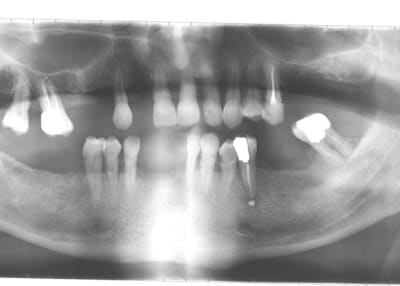

patient qui vient pour un détartrage et un contrôle.

hygiène correcte, va voir un dentiste de façon régulière.

moi j'annonce les mauvaises nouvelles.

je comprends pas, pourtant j'ai été souvent chez mon dentiste, j'ai toujours fait tout ce qu'il m'a dit de faire.

comment ça se fait que j'ai les dents en si mauvais état?

tu veux les points sur les i,mac,l'erreur des traitements canalaires ,ayant provoqué,des pêches,je ne pense pas que celles ci soient antérieures au traitement

erreur de ne pas avoir reconstuitué une occlusion acceptable,ce qui a accéléré l'egression des molaires supérieures droites,et surement d'autres

problèmes coté gauche

erreur de ne pas avoir traité le problème paro,mais que vas tu faire à ce stade pour le corriger?

c'est ce que je vois en première lecture sur cette pano,assez explicite,mais pas suffisante